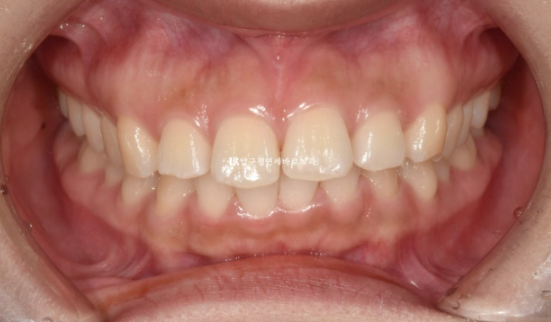

앞니 돌출로 교정을 위해 찾아온 환자분입니다.

24.02

앞니 좌우 높낮이가 다른 것이 보입니다.

어금니 교합은 좋습니다.